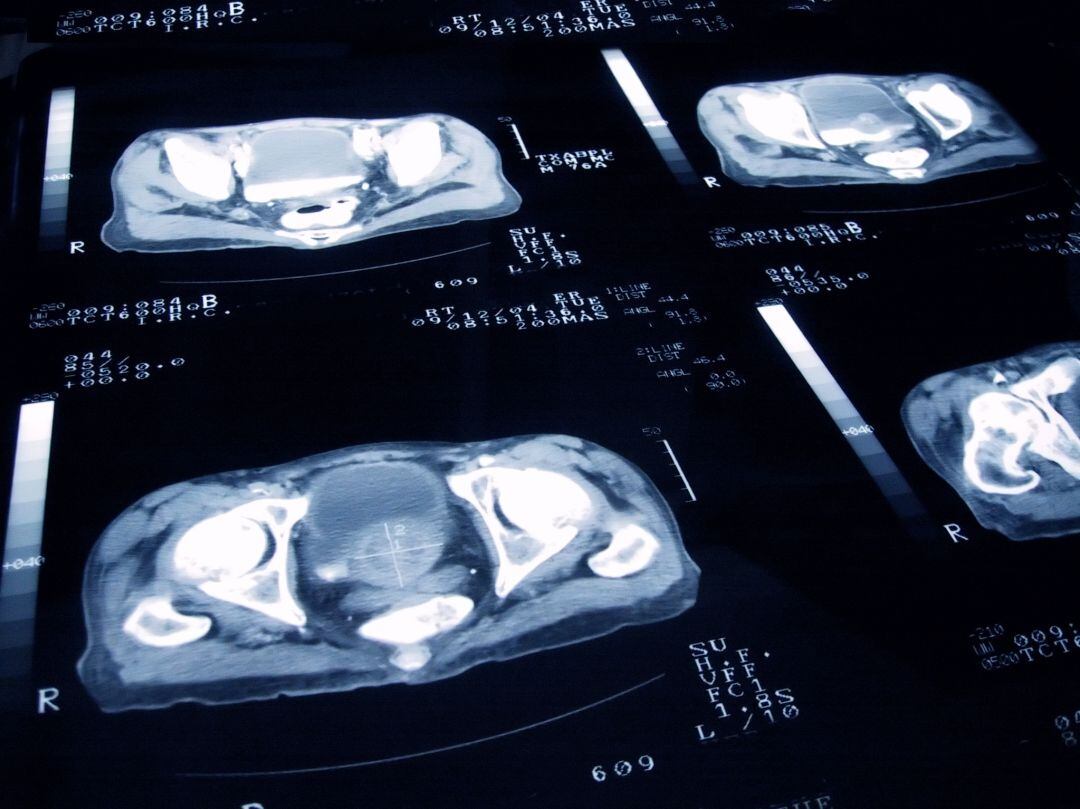

Uno de cada seis varones desarrollará cáncer de próstata a lo largo de su vida / Getty Images